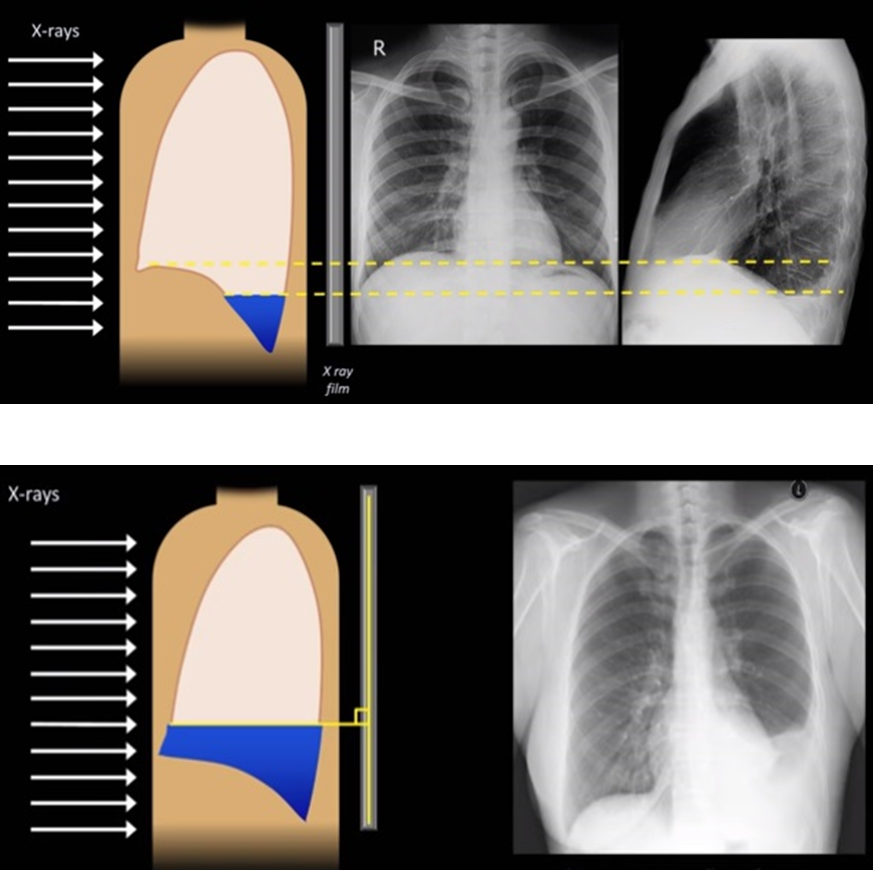

Pleural Effusion

____ is defined as the accumulation of fluid in the pleural space.

____ is seen in the costophrenic angle only (seen on Lat. views), unless it is a high level ___ (Lat. and PA views).

Subpulmonic effusion

____ is an accumulation of fluid between the lung base and diaphragm. It does not blunt the costophrenic angles.

Hemothorax

_____ is a collection of the blood within the plural space (between visceral and parietal layers).

This pathology typically has an attenuation of 35-70 HU.

Pleural effusion typically has an attenuation of 5-14 HU.